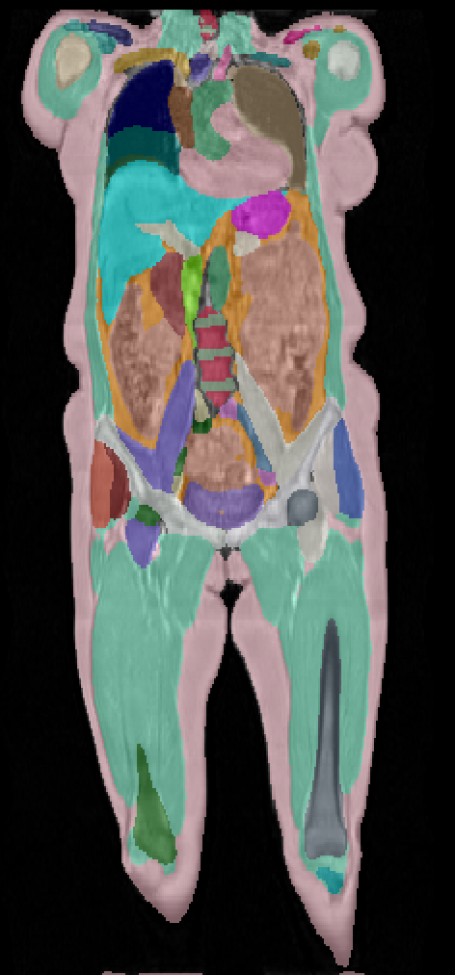

\captionof

figureUKBOB Size and Diversity. Our proposed UK Biobank Organs and Bones (UKBOB) is the largest labeled medical imaging dataset for segmentation, comprising body organs of 51,761 MRI 3D samples (17.9 M 2D images) and a total of more than 1.37 billion 2D masks of 72 organs. Left: we show label examples from UKBOB from axial, coronal, and sagittal views. Right: We show a plot of the size (number of 2D images) and diversity (number of classes) of our UKBOB compared to other medical images datasets. The size of the bubbles indicates 2D image resolution. This new scale in dataset size and diversity should unlock a new wave of applications and methods in the computer vision and medical imaging communities.